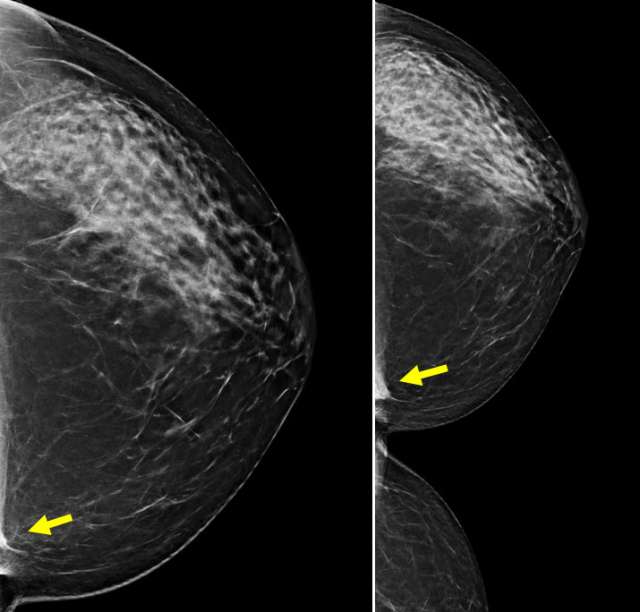

Case: Sternalis Muscle Figure 3

Left: CC view of the left breast shows a medial asymmetry, partially visualized. Cleavage view: Asymmetry is triangle shaped and abuts the chest wall, consistent with sternalis muscle.